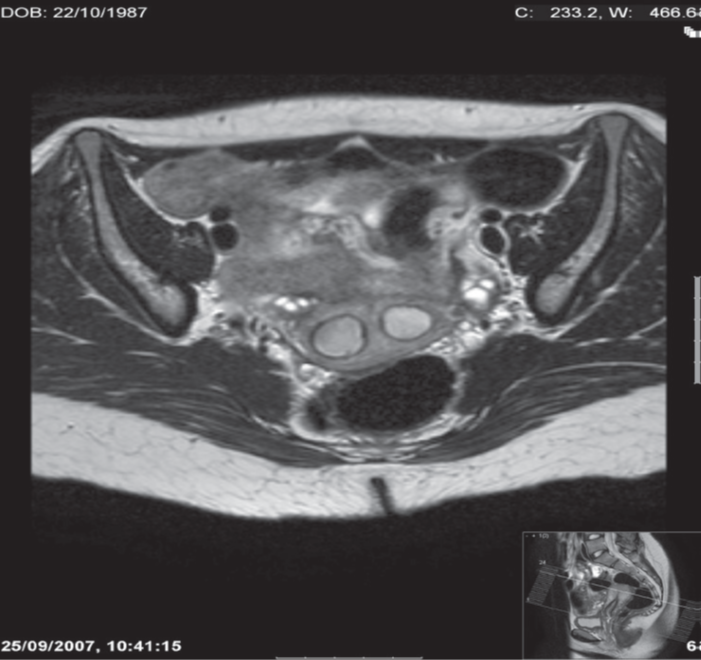

Axial MRI .

The endometrial cavity is divided into two compartments by a septum of myometrium